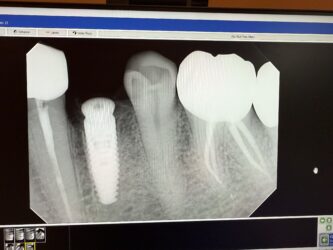

Looking for some feedback and advices. #21 was extracted and placed immidate 4.1×12. I know I needed to go 2-3 mm beyond the apex, however, I didn’t have the correct length. The final torque was about 20 NCM. Bone graft was added and collagen plug and sutured with chromic gut. Please evaluate the radiographs and advise. When should I schedule for follow up?

Everything looks fairly solid on the xray to me. I would follow up 4 weeks post op and see how things are progressing.